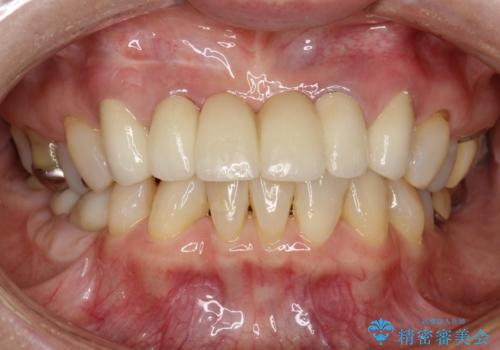

- 仮歯の製作、古い土台(メタルコア)の除去まで行い、根管治療は専門医に依頼

→根管治療終了後、ファイバーコアを築造し、新しいセラミックブリッジを製作した。

かぶせ物の種類:PFZ standard